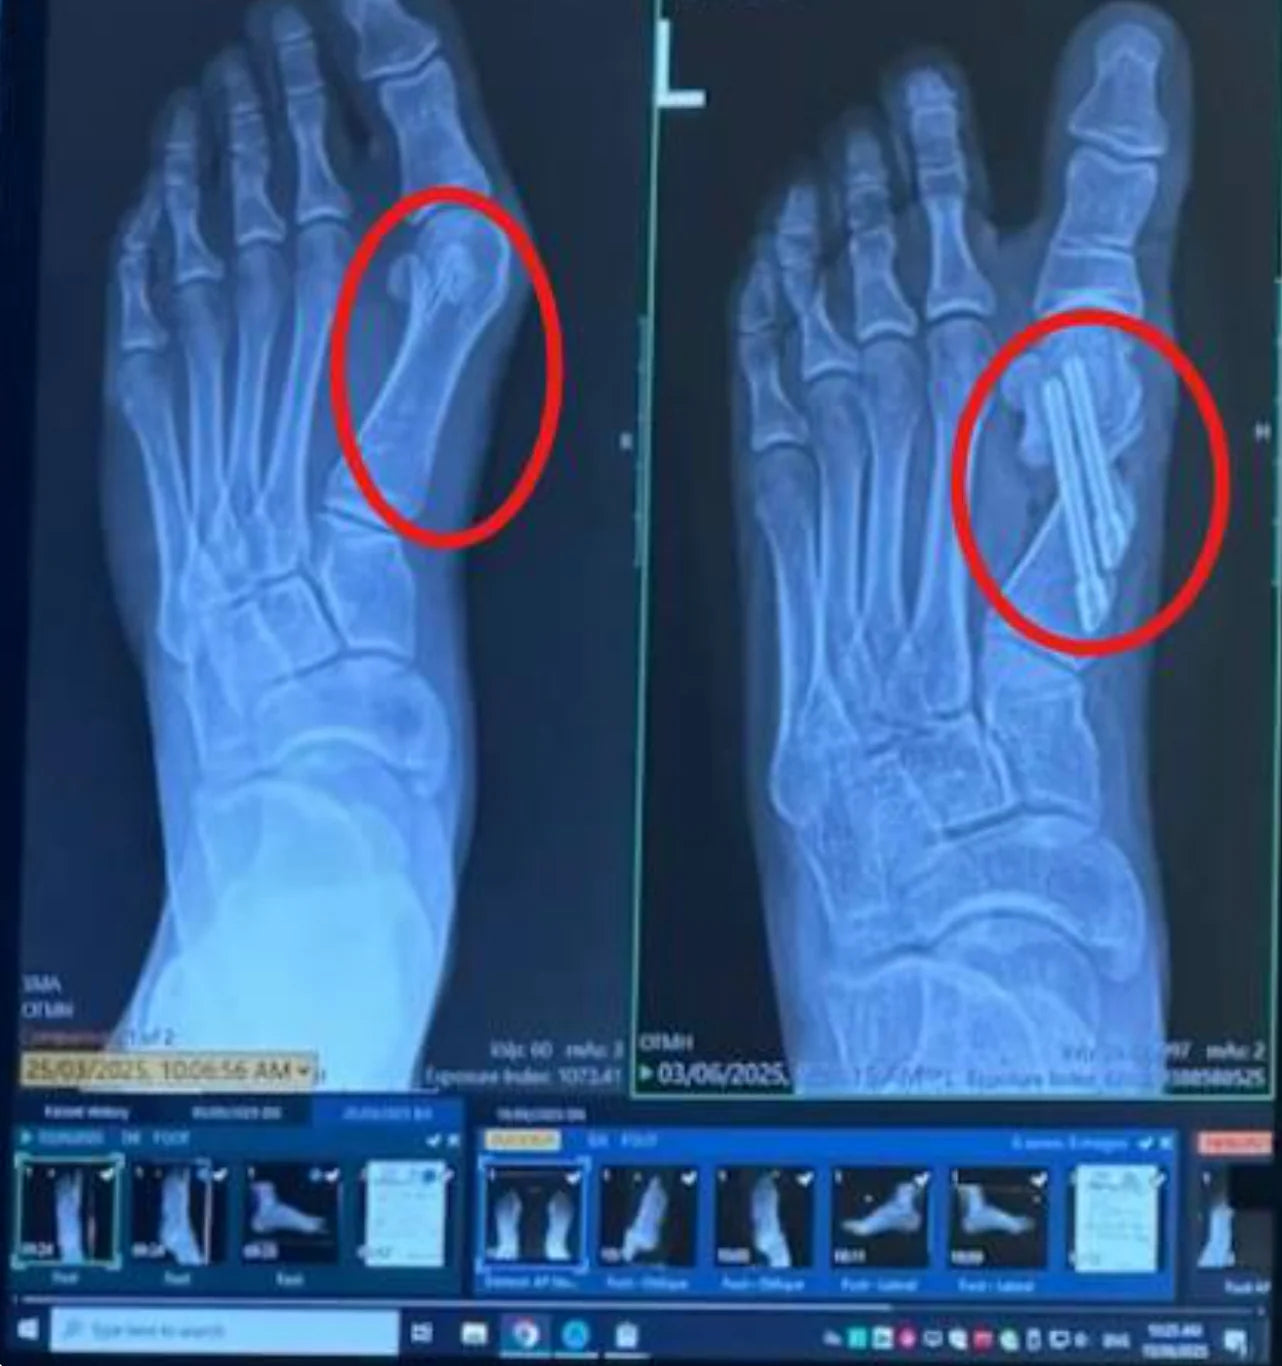

Waarom Operaties Aan de Grote Teen Mislukken

30 tot 50% van de operaties aan scheefstaande grote tenen mislukt of resulteert in langdurige stijfheid, littekenweefsel, of terugkerende pijn.

Herstel? Verwacht 6 tot 12 weken zonder op je voeten te kunnen staan, krukken, en het risico op herhaling als je niet de rest van je leven orthopedische inlegzolen draagt.

Deze operaties pakken het echte probleem niet aan. Ze snijden simpelweg en gebruiken schroeven om je teengewrichten opnieuw vast te maken.